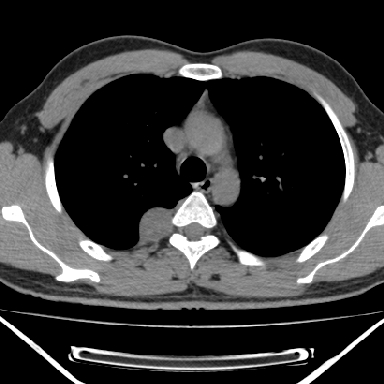

m 30 右胸痛10年

病灶与椎间孔间存在脂间隙,病灶较大,椎间无明显异常改变,与胸膜移行处可见尾状影,考虑胸膜肿瘤,以良性间皮瘤可能性大

病灶最大径线处于肋间隙,不排除起源于肋神经源性肿瘤

右上后纵隔旁软组织肿块影,与肺界面光滑,与胸壁呈钝角相交,提示肺外病变。位于肋骨下缘,边缘清楚,呈三角样指向与右侧椎间孔,但并示进入椎间孔;与对侧神经根对比,属同一走行方向。

右上后纵隔脊柱旁类圆形肿块,边界光整,与胸腔呈钝角,首先考虑来源于纵膈,神经源性肿瘤可能大。

以下是引用余辉在2007-1-26 10:55:00的发言:[br][br]病灶与椎间孔间存在脂间隙,病灶较大,椎间无明显异常改变,与胸膜移行处可见尾状影,考虑胸膜肿瘤,以良性间皮瘤可能性大

支持, 椎体及附件未见破坏!

良性胸膜间皮瘤可能性大,神经源性肿瘤可能性小,因为没有见到有瘤体组织伸入神经孔内!

右上后纵隔脊柱旁见长椭圆形肿块,边界光整,与胸壁呈钝角。周围骨质未见异常。

考虑、1、后纵隔神经源性肿瘤;

2、不除外单发胸膜间皮瘤。